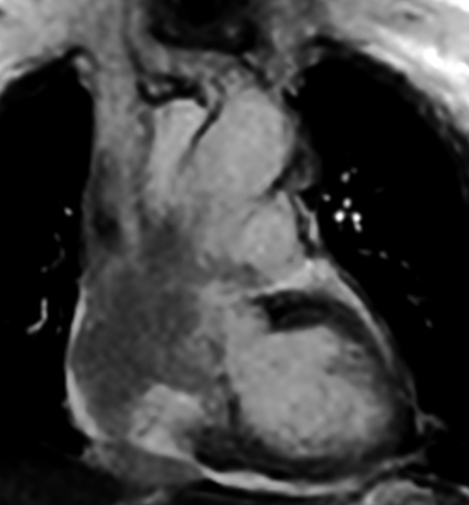

Four Chamber showing the mass projection to vital structures